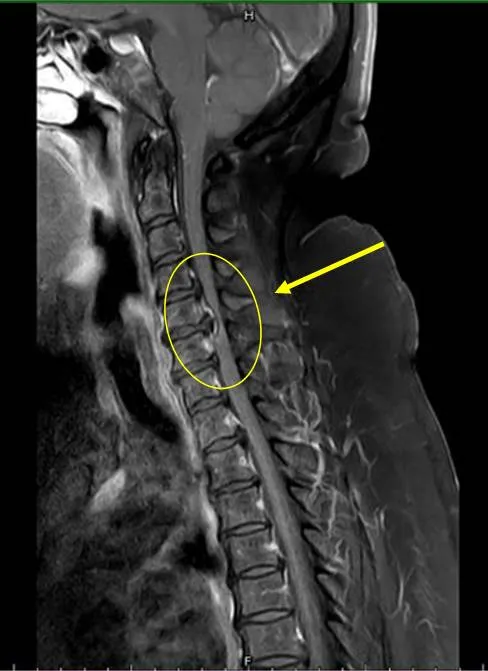

經頸部核磁共振檢查,發現患者頸椎壓迫很嚴重,立即安排頸椎融合手術來改善神經壓迫狀況。豐原醫院提供

豐原醫院表示,這名47歲的吳小姐長期腰酸背痛不適,近三個月開始下肢無力、麻痛,無法工作,甚至須使用四腳拐杖協助才能走動,在先生陪同至該院神經外科門診求治,經醫師做神經學評估及安排頸部核磁共振檢查,發現頸部退化椎間盤突出導致壓迫神經使肢體麻痛無力。

神經外科張正一醫師也表示,身體為了平衡駝背,易導致頭部自動往前移,讓肩頸痠痛產生,外觀上易變成「永久低頭族」,如此易傷頸椎,提醒民眾造成下肢無力會有許多原因,必要時盡早求醫做檢查,甚至與醫師討論自身狀況,或許會有意外的發現,才能徹底改善原因,達到治療效果。